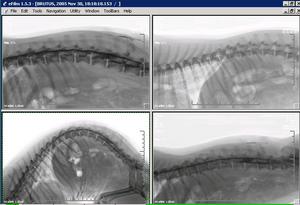

SOPORTE:varias radiografías en el mismo soporte plástico |

DICOM. La imagen DICOM se puede examinar de múltiples formas: ampliando, en copia negativa, realzando , etc.. Sólo se puede manejar con software DICOM. |

JPG: La imagen DICOM se puede exportar en formato convencional JPG para que se pueda leer con cualquier visor. |

NEURORADIOGRAFÍA: En neurología es de gran ayuda muchas veces el realizar copias en negativo para la observación de los contrastes mielográficos. |

OTROS FORMATOS DE IMPRESIÓN: |